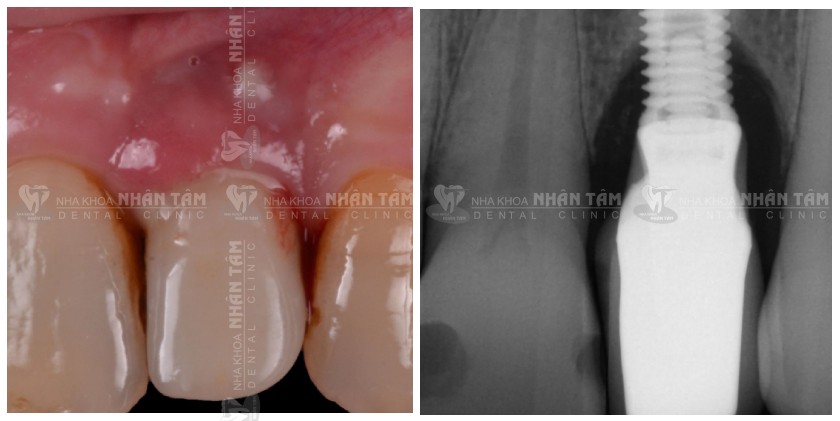

Tình trạng ban đầu: Bệnh nhân có cảm giác đau nhức, khó chịu, chảy máu và chảy mủ ở vùng răng trước. Sau khi kiểm tra trong miệng cho thấy túi sâu xung quanh Implant R22, và phân tích hình X-quang cho thấy tình trạng tiêu xương ở mức độ vừa phải.

Tình trạng ban đầu: túi sâu & tiêu xương mức độ vừa